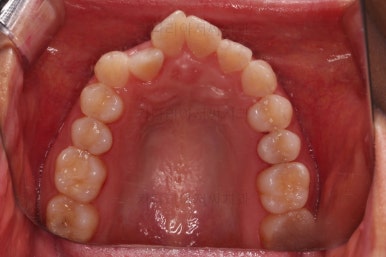

부산교정잘하는치과 초진 시 입안의 모습입ㄴ디ㅏ.

앞니 쪽이 위아래가 다 삐뚤고, 위에 작은 앞니 하나가 거꾸로 물리는 상태였습니다.

종료 시 사진입니다.

중앙선, 교합, 치아배열 모습 모두 양호해졌습니다.

부산교정잘하는치과 전후 비교해 보겠습니다.

치열도 당연히 좋아졌지만 웃을 때 보이는 치열도 매우 예뻐졌습니다.